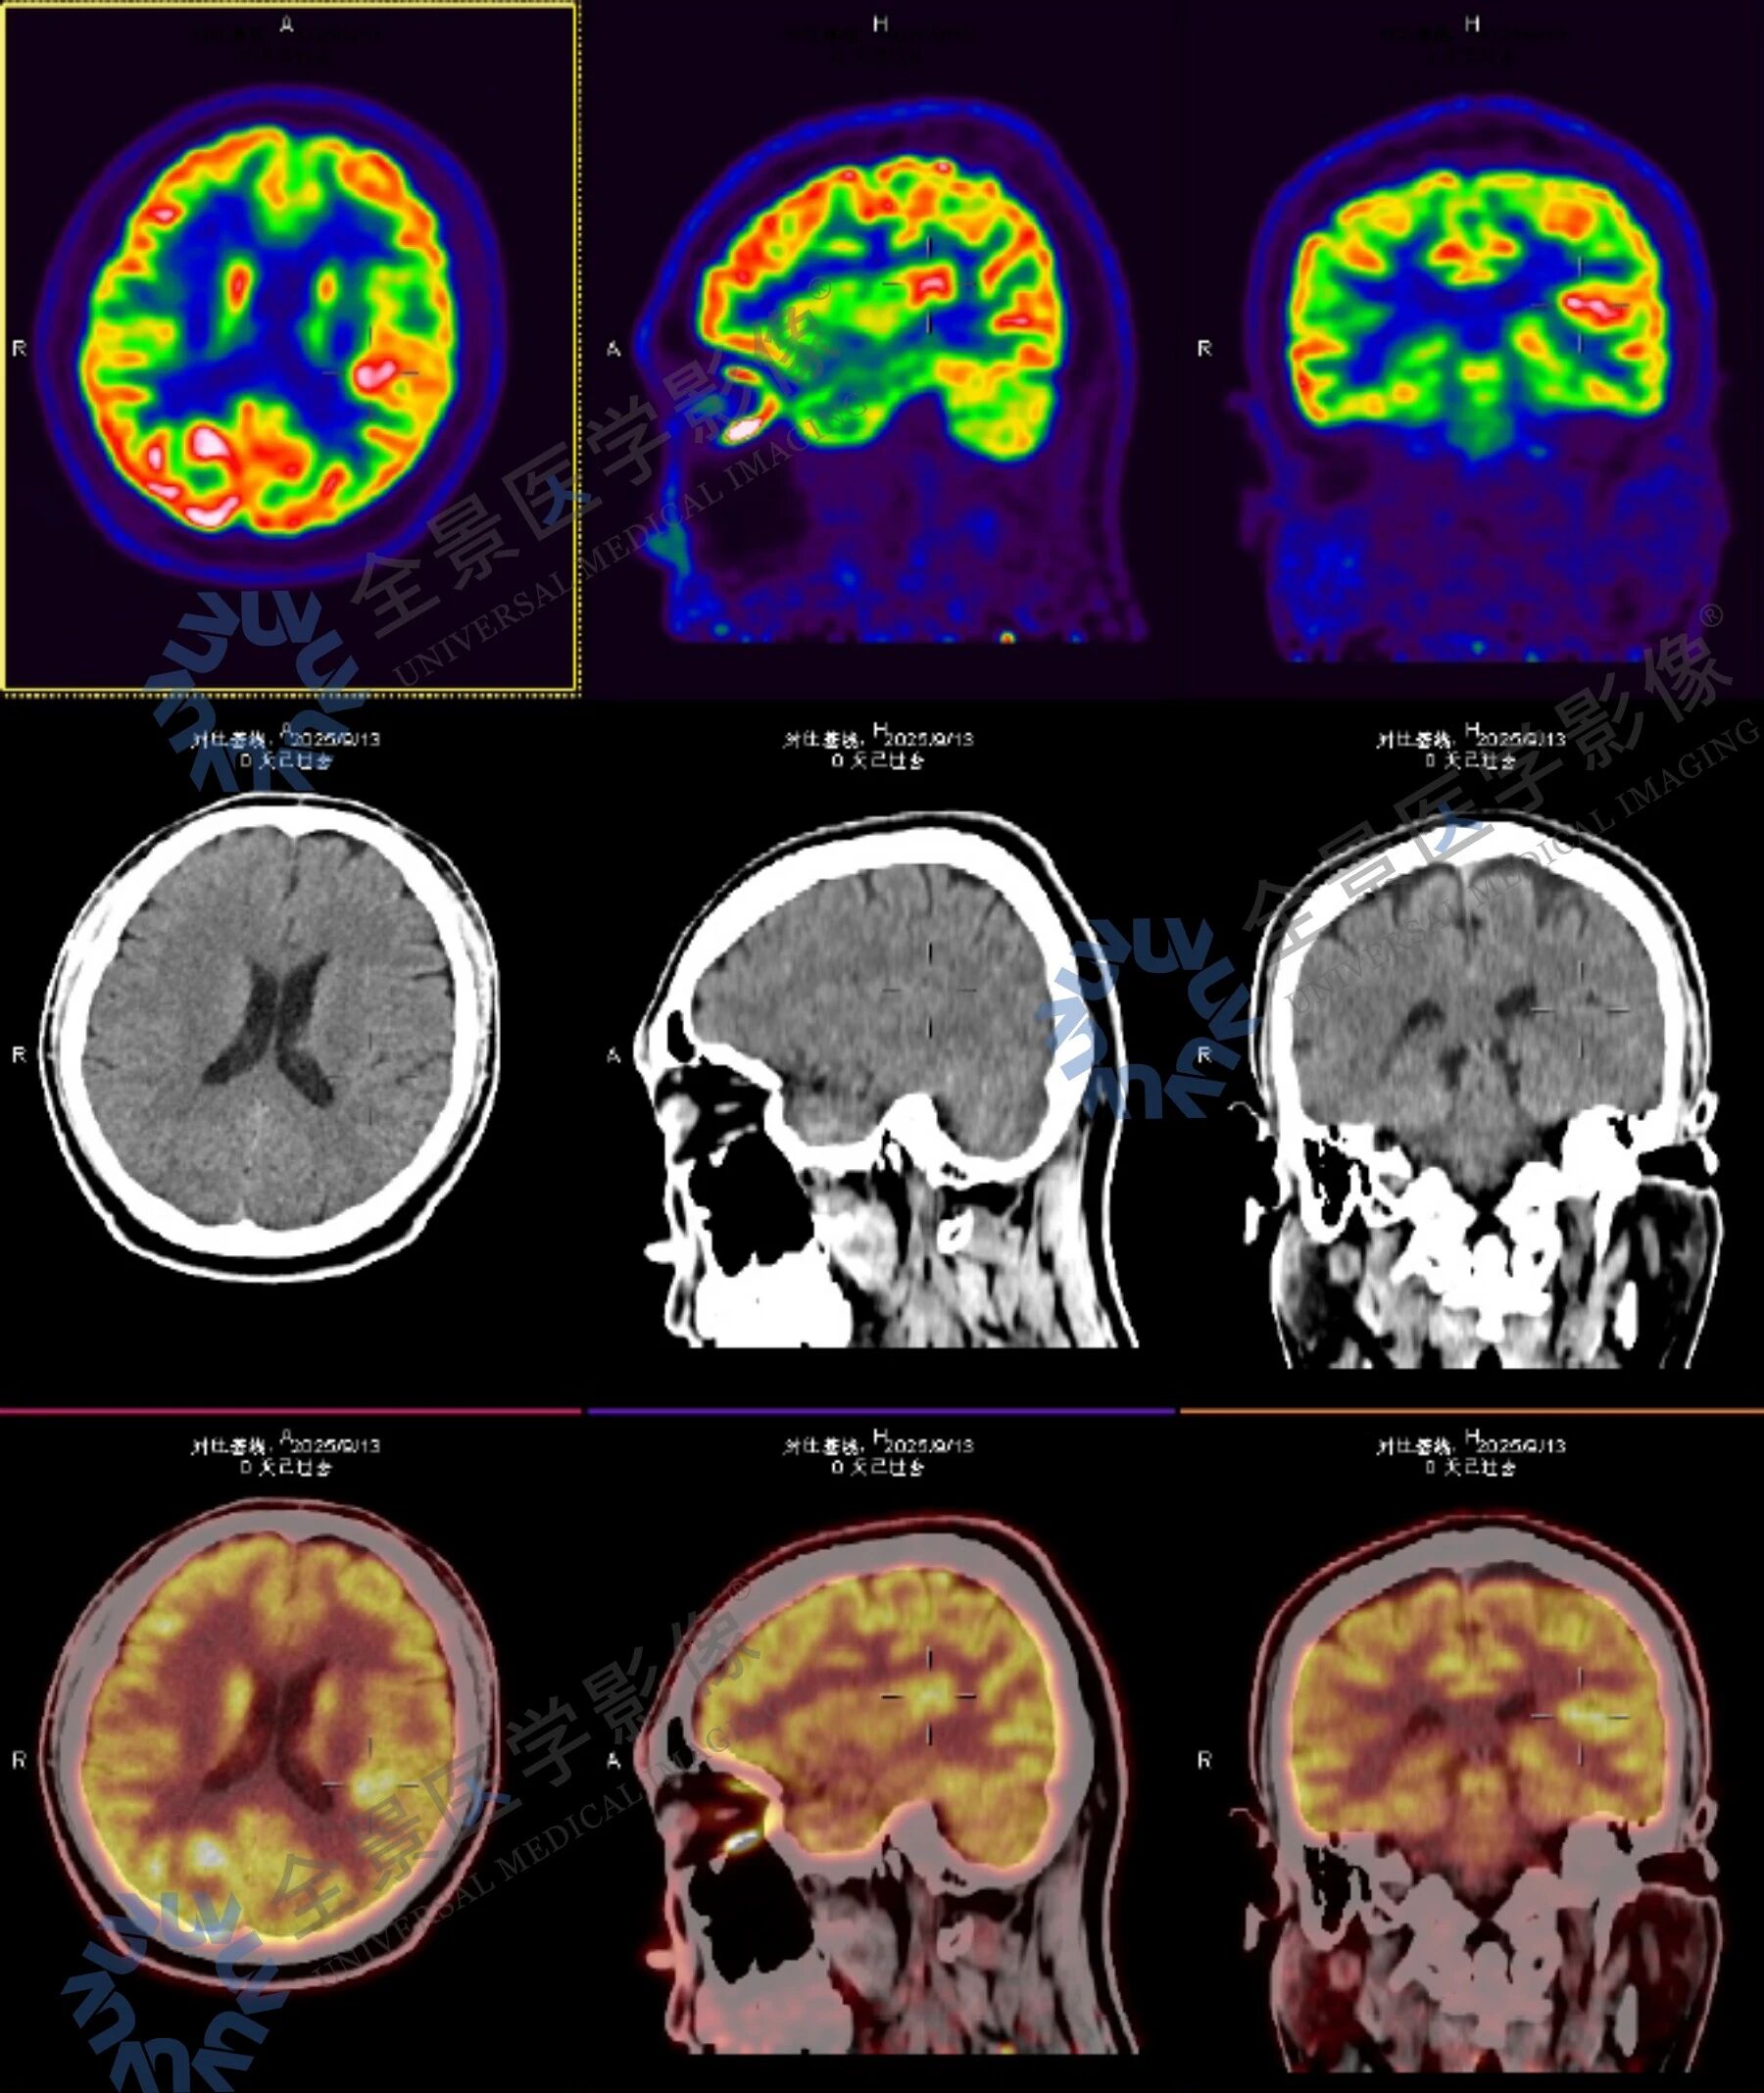

考虑到病症复杂,全景安排门诊部主任与影像主任联合问诊,结合病史和症状,影像主任建议在无创检查前提下,采用结构影像、血流灌注与代谢功能的多模态联合检查,通过脑部 MR 平扫、ASL 脑血流灌注成像与脑部 PET-CT 的融合,实现精准定位与定性诊断。

脑部核磁+ASL 脑血流灌注成像显示:

左侧基底节区异常信号,考虑术后改变,局部脑软化灶周围胶质增生;相应区域 ASL 示灌注稍减低。

脑部 PET-CT 扫描显示:

病灶前缘 MR 异常信号增高,考虑局部神经胶质增生表现;左侧上额叶中部深层较小的类圆形代谢轻中度增高灶及左侧颞叶中部后内侧小片状轻中度代谢增高灶。

结合影像检查结果与临床表现,考虑上述三个部位与头晕发作关系密切,提示存在癫痫可能,以左侧颞叶中部后内侧代谢增高灶为主要病变部位。